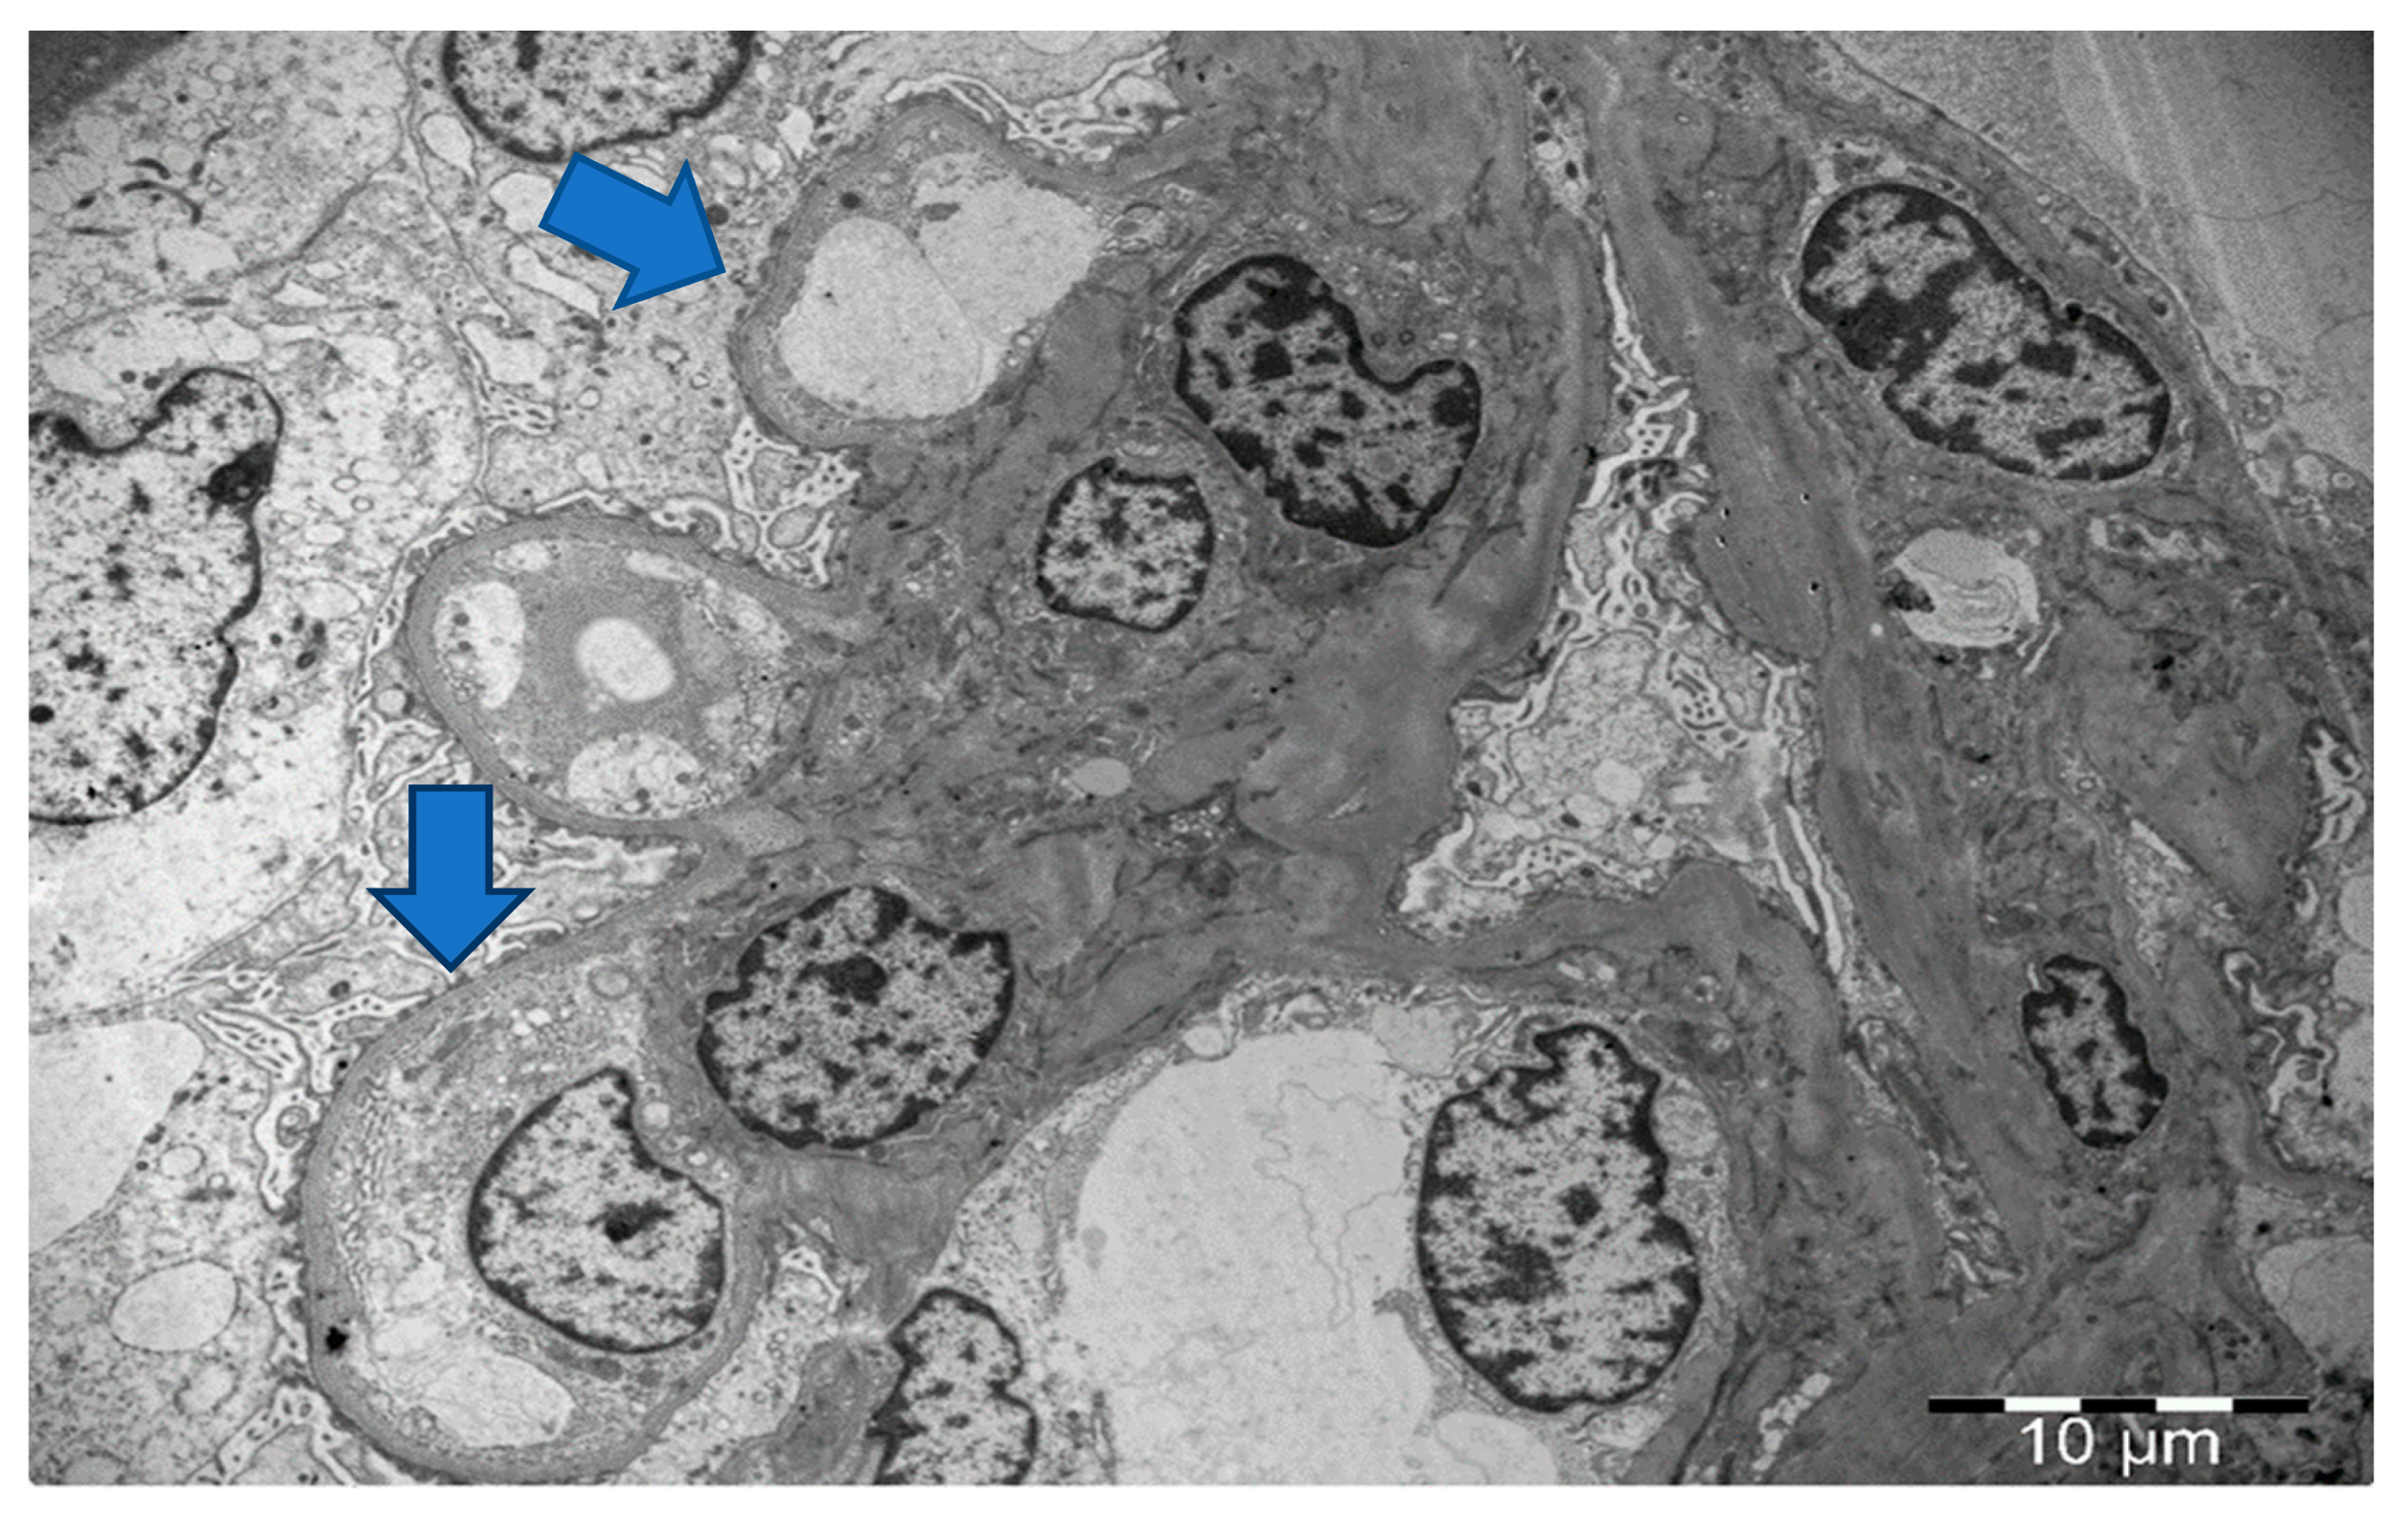

2. Case 1 Description: MCD Associated with Tamoxifen